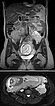

Koronare (oben) und axiale (unten) T2-gewichtete, fettunterdrückte Haste-Sequenzen ohne Kontrastmittel bei der Erstuntersuchung vor der Schwangerschaft.